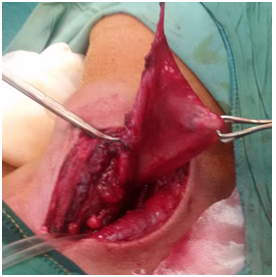

All six patients were symptomatic Four of patients were male. Age of patients was 65 to 80years. Four of patients came with dysphasia aspiration, halitosis, and malnutrition and regurgitation, one of this patient present three period with aspiration pneumonia and hospital admission. One of patients underwent endoscopic diverticulotomy and 24 hour after this procedure present with odynophagia, fever and neck subcutaneous emphysema With B-swallow perforation of diverticula was demonstrated, this patient underwent neck exploration and diverticulectomy and drainage. Diagnostic tools of five cases was B-swallow and esophagoscopy (Figures 1-5). One came with food marital retention and pain and neck mass tender mass. One patients referred with erithem, redness and criptation of neck with diagnosis of diverticulitis (Figures 6 & 7). Two cases underwent flexible endoscopic diverticulotomy, one failed and another ones complicated with perforation. The most common surgical approaches was diverticulectomy and myotomy in four patients (Figures 8 & 9). Food debris was present in one patient (Figure 10). Two of patients underwent diverticulectomy without myotomy. Complication and mortalities were zero. In two years flow-up, Outcome was good.

Figure 8 Show swallow pouch of huge Zenker's diverticulum after opening.

Figure 9 Show swallow pouch of huge Zenker's diverticulum after opening.